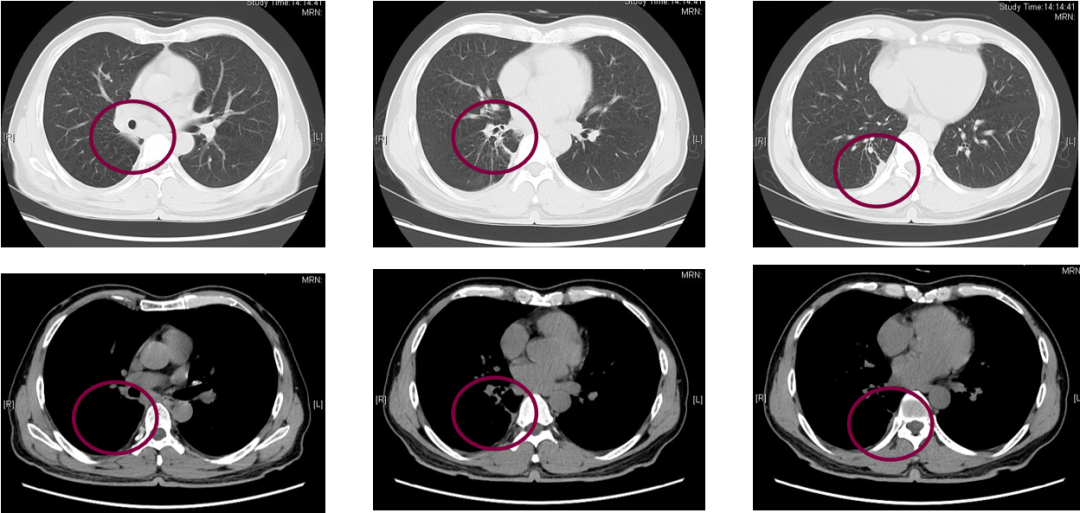

胸部增强CT(2020年3月6日):如图2-1所示,右肺上叶后段占位,最大径为68mm,伴邻近胸膜增厚及右侧第5、6骨质破坏,考虑肺癌,侵犯胸膜及右侧第5、6肋骨,建议CT增强检查。右肺中叶内侧段胸膜下小结节;右肺上叶大片感染灶;双肺多肺段增殖钙化灶、炎症。

图2-1:基线期胸部CT

影像学及疗效评价:联合治疗2周期后(2020年5月9日)胸部CT复查如图2-2所示,右肺上叶靶病灶最大径为30mm(治疗前靶病灶最大径为68mm),非靶病灶(纵隔淋巴结、胸膜、骨转移灶)仍可见,其中纵隔淋巴结病灶较前有所缩小。总体疗效评价PR。

图2-2:免疫联合化疗2周期后胸部CT

联合治疗6周期后(2020年8月4日)胸部CT复查见右肺上叶靶病灶最大径为29mm,非靶病灶(纵隔淋巴结、胸膜、骨转移灶)仍可见,纵隔淋巴结病灶较前有所缓解。总体疗效评价维持PR。

影像学及疗效评价:单药维持治疗11周期后(2021年2月28日)胸部CT复查如图2-3所示,右肺上叶靶病灶最大径为16mm,非靶病灶(纵隔淋巴结、胸膜、骨转移灶)仍可见。总体疗效评价维持PR。

图2-3:免疫维持治疗11周期后胸部CT

本例患者以“右侧胸痛1月余,确诊右肺癌12天”来诊,诊断右肺肉瘤样癌Ⅳa期(cT3N2M1b)伴纵隔淋巴结、胸膜、骨转移,驱动基因阴性,PD-L1阳性,ECOG PS评分0分。经患者充分知情同意后,一线予患者替雷利珠单抗联合化疗后序贯为免疫单药维持治疗。患者经替雷利珠单抗联合治疗2个周期后,右肺靶病灶最大直径从68mm减少至30mm,瘤体缩小50%以上;纵隔淋巴结病灶较前有所缓解,总体疗效评价达到PR。联合治疗6个周期后,患者总体病情平稳,疗效维持在PR,治疗过程中曾出现过骨髓抑制,考虑化疗引起,予对症处理后可缓解。患者第二阶段予替雷利珠单抗单药维持治疗,用药至今已11周期(共17周期),右肺靶病灶较前进一步缓解,纵隔淋巴结病灶及骨转移病灶平稳,胸水明显减少,总体疗效持续稳定在PR,获得了较为持久的免疫应答,且单药维持期间未出现严重不良反应。截止发稿时,患者无进展生存期已达到1年余。

图2-4:病例二治疗方案及疗效评价